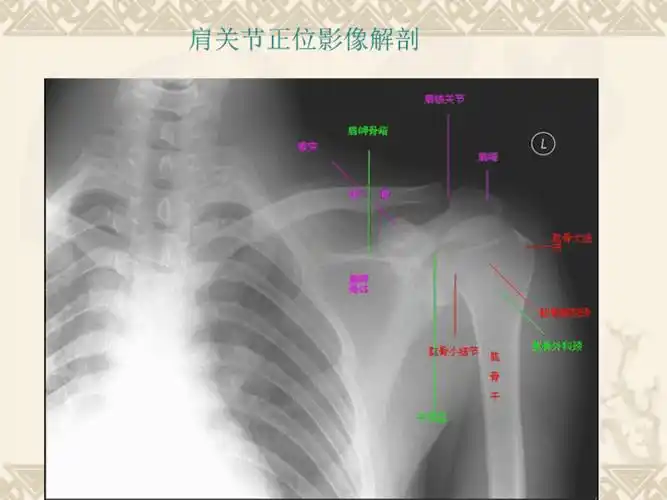

肩关节的摄影体位